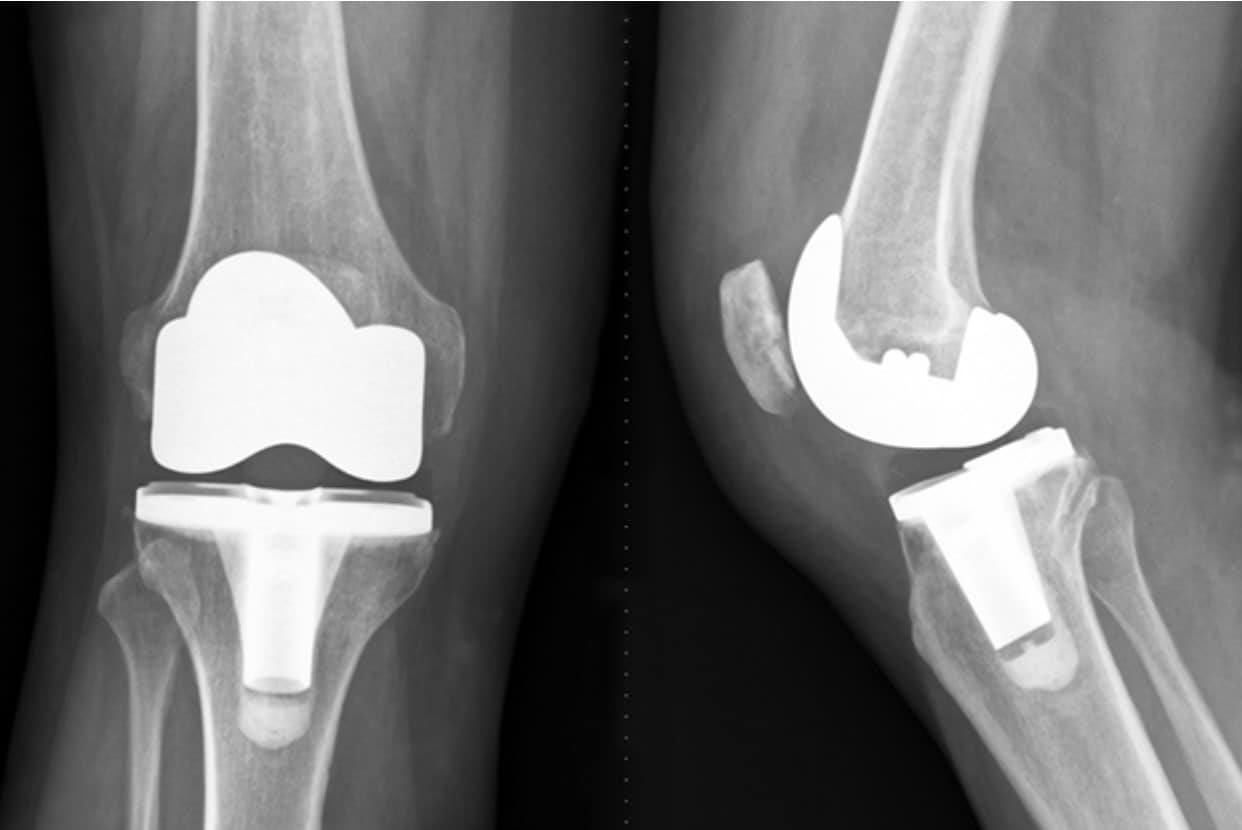

Total knee arthroplasty (tka) or total knee replacement (tkr) is a common orthopaedic surgery that involves replacing the articular surfaces (femoral condyles and tibial plateau) of the knee joint. Initiate gentle strengthening exercises with the primary goal of activating the quadriceps. Tka consists of resection of the diseased or degenerative articular surfaces of the knee, replacing the surface with metal and. Exercises you do before knee replacement surgery can strengthen your knee, improve flexibility, and help you recover faster. There are numerous exercises you can. In this article you will learn all about the critical steps to take immediately after a total knee replacement surgery including pain and swelling management, assistive devices, as well as. During stage i, continue with rice (rest, ice,. Your orthopaedic surgeon and physical therapist may recommend that you exercise for 20 to 30 minutes daily, or even 2 to 3 times daily; If nonsurgical treatments like medications and using walking supports are no longer helpful, you may want to consider total knee replacement.